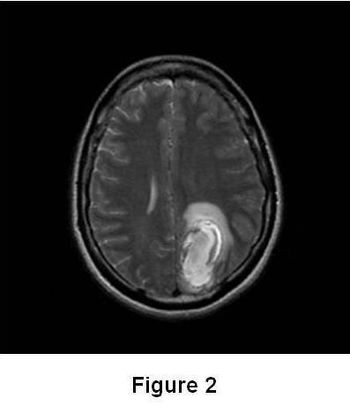

Experts discuss the case of a 56-year-old white man who presents with multiple immune-related adverse events